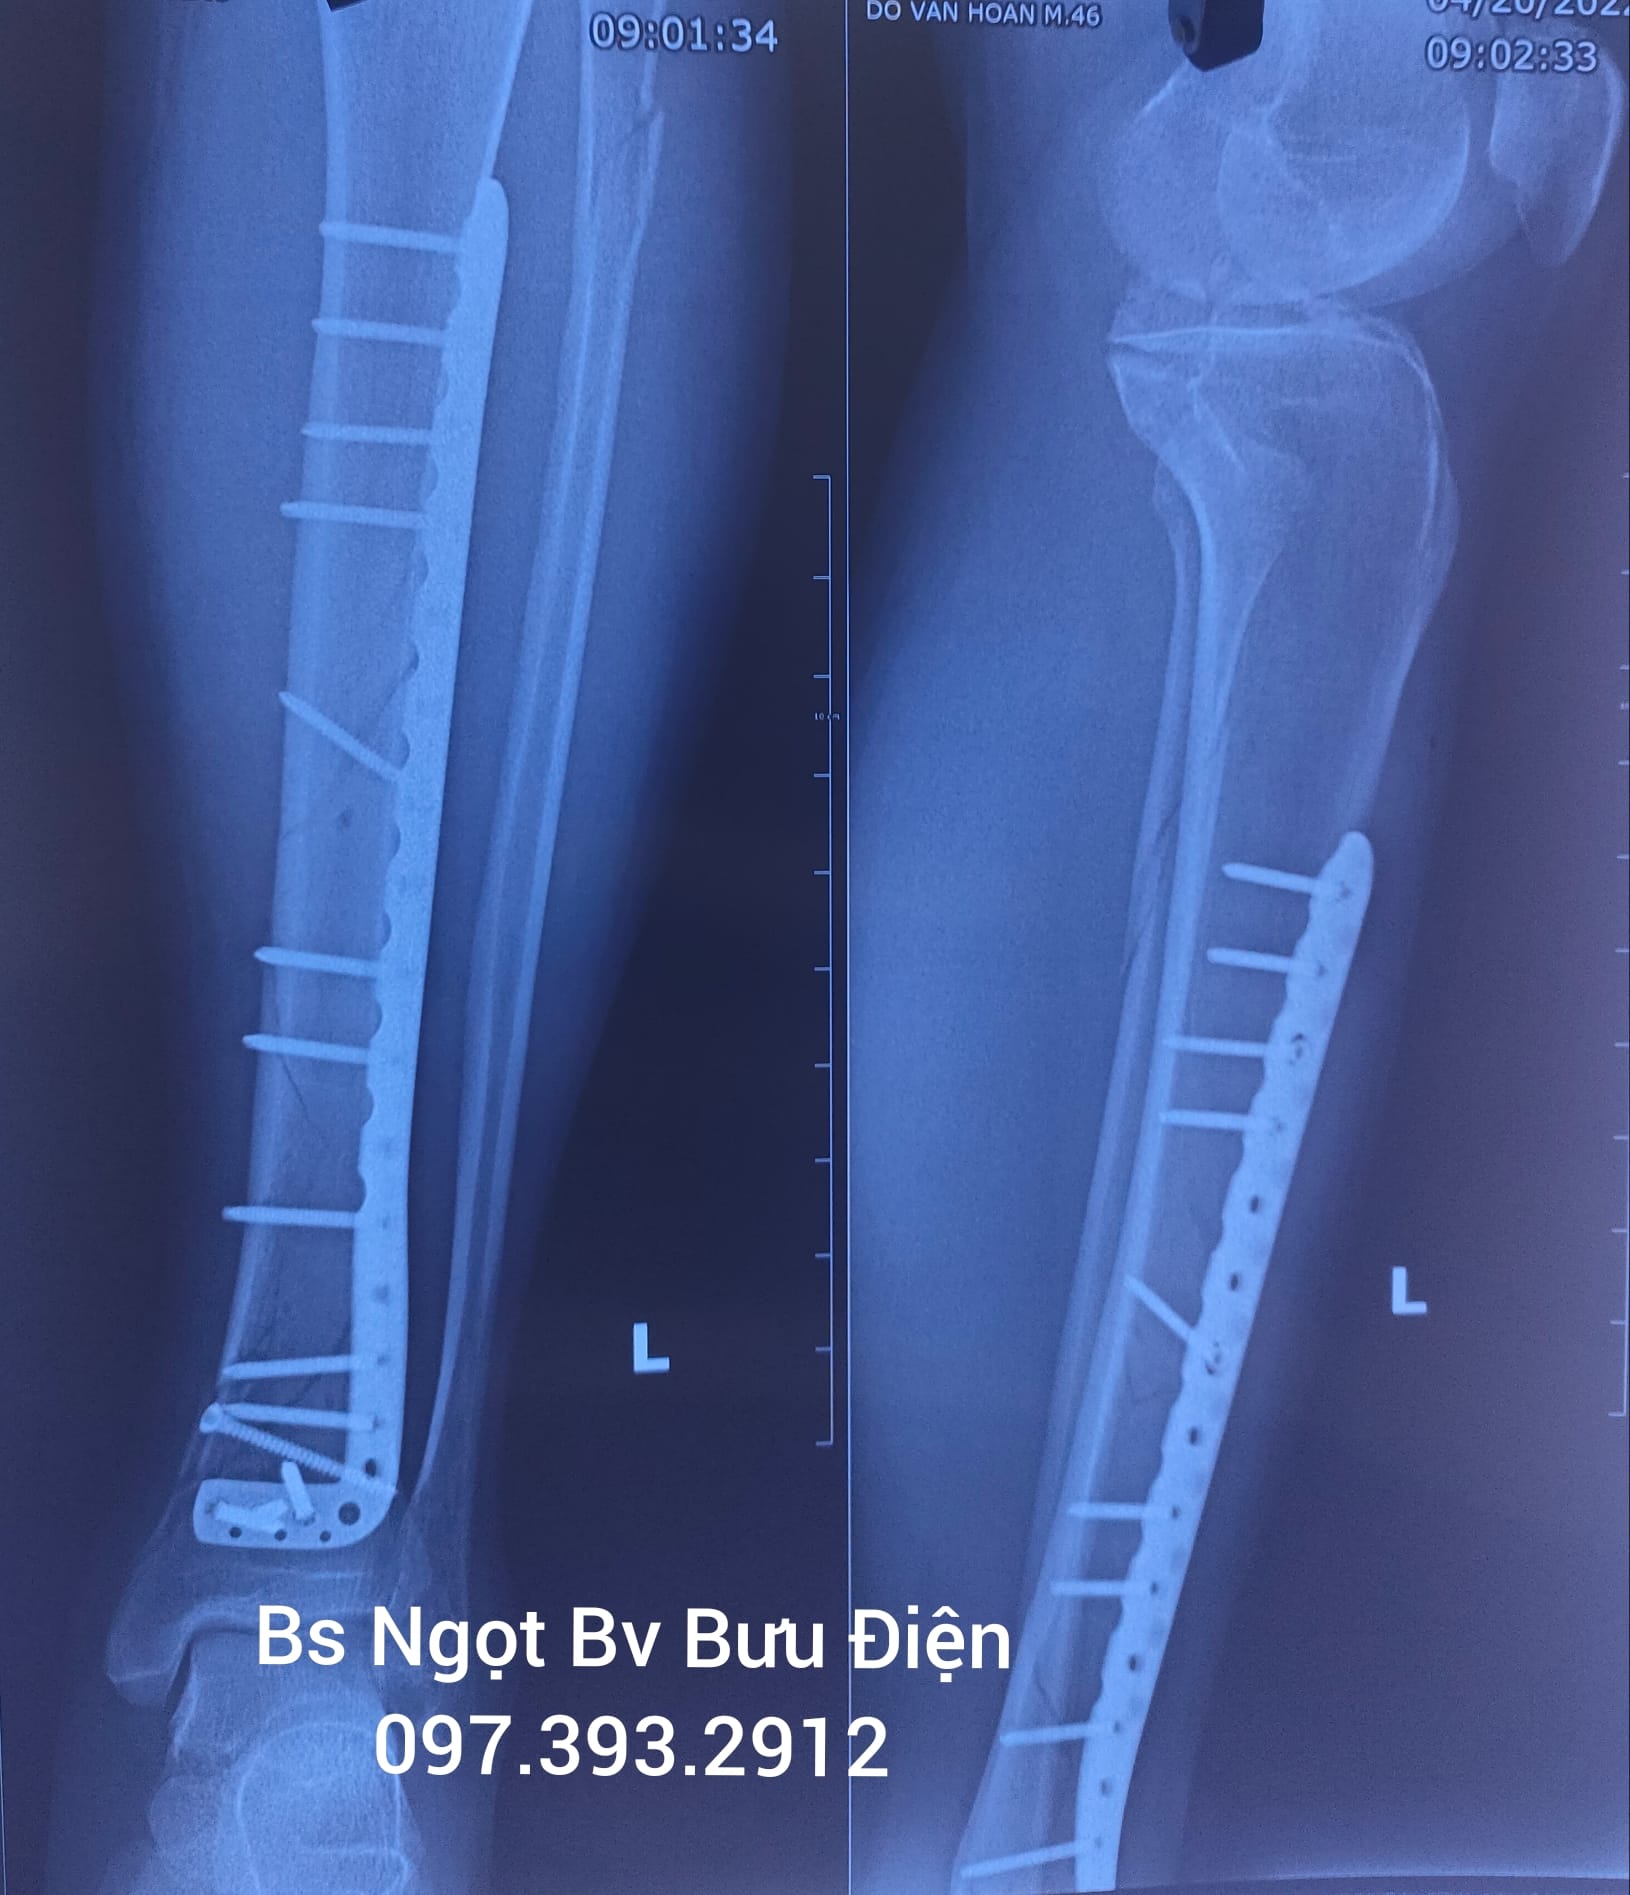

3.3. Phẫu Thuật Thay Thế Khớp (Arthroplasty)

Khi các phương pháp bảo tồn thất bại và chất lượng cuộc sống bị suy giảm nghiêm trọng do đau đớn và mất chức năng (thường gặp trong thoái hóa khớp giai đoạn cuối), phẫu thuật thay khớp (toàn bộ hoặc bán phần) là lựa chọn tối ưu. Sự tiến bộ trong vật liệu cấy ghép và kỹ thuật phẫu thuật ít xâm lấn đã cải thiện đáng kể tỷ lệ thành công và thời gian phục hồi của bệnh nhân.